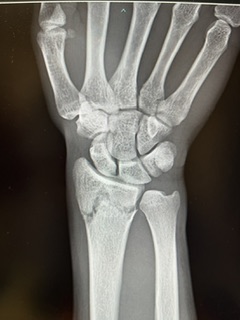

2週間前にバスケットボールでジャンプ後に手を衝いて転倒して右橈骨遠位端骨折をした学生です。

2日前にプレート固定の手術をしてもらいました。術後が一番痛かったそうです。今も浮腫があり痛いそうです。